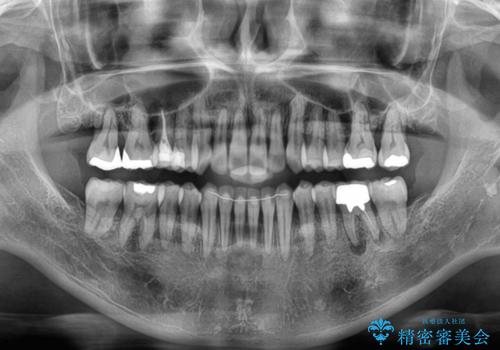

- 前歯のデコボコや八重歯を治したいとのことで来院された患者様です。

受け口傾向の骨格であり、前歯はクロスバイトまたは切端咬合となっており、下顎を中心に歯列全体の後方移動を行い、IPR(歯と歯の間を削る)によってデコボコが解消するように設計し、インビザラインにより治療を行うこととしました。

受け口傾向のインビザライン矯正は比較的治療を行いやすいため、きれいに仕上げることができました。舌の突出癖が顕著であったため、改善のためのトレーニングをしっかりと行っていただきました。